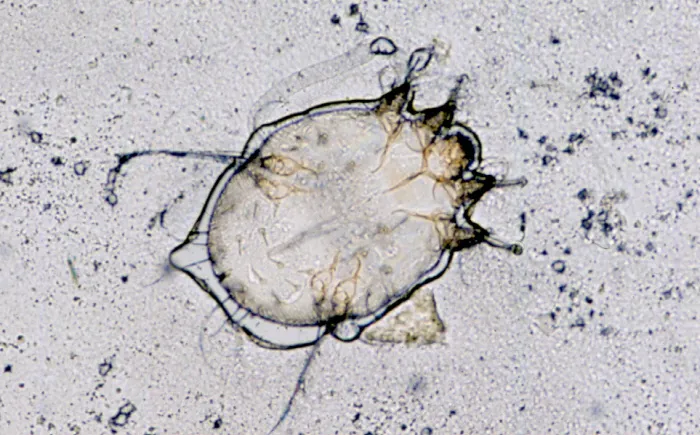

◾ 피부 긁어내기 검사 : 피부를 긁어내어 현미경으로 관찰함으로써 진드기, 알, 배설물 등의 존재를 확인할 수 있습니다.